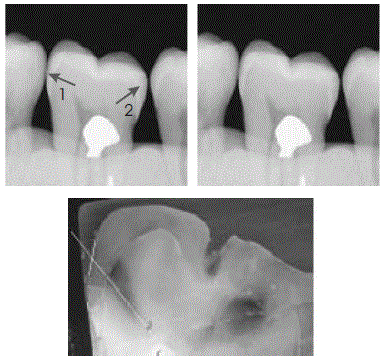

Enunciado 1881473-1

The Journal of Contemporary Dental Practice, vol. 7, n.º 4, set./2006.

Muitos fatores responsáveis pelo processo de polimerização podem afetar negativamente a integridade do complexo dente-restauração. O uso de materiais restauradores adesivos não é garantia de restaurações de confiança. Atualmente, o clínico convive com problemas de contração de polimerização, stress de contração de polimerização e restauração etc. A figura acima diz respeito ao fator C, que deve ser observado na aplicação da técnica restauradora. Assinale a opção incorreta acerca da contração de polimerização, considerando as informações apresentadas.

Enunciado 1881472-1

Caries Research, v. 38, p. 34-8, 2004.

As imagens radiográficas ilustradas acima são relativas a uma mesma situação clínica e seu correspondente histológico. Considerando essas imagens, julgue os itens a seguir.

I A imagem radiográfica da superfície distal do molar apresenta lesão cariosa de esmalte Enunciado 1881472-2.

II A imagem radiográfica da superfície mesial do molar apresenta lesão em esmalte e dentina Enunciado 1881472-3.

III A lesão em dentina, presente na situação clínica acima, corresponde a lesão cavitada.

IV Há tratamento não-operatório adequado para a situação clínica acima.

Estão certos apenas os itens